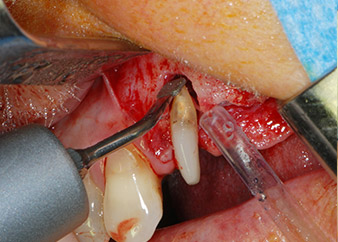

One month later, on the day of surgery, pain and inflammation at tooth 24 were minimal, but mobility of Miller class 2 was still present. After opening the flaps and cleaning the periapical and peri radicular infected tissue, the extent of the bone defect became obvious (Figs. 2 and 3).

At the buccal root, all vestibular and distal bone was missing. Attachment was essentially restricted to the palatal root, underlining the preliminary poor prognosis. Tooth 27 also showed a reduced horizontal attachment and a minimal apical rarefaction (cf. Fig. 1) without clinical symptoms.

However, we maintained our initial plan to retain both teeth as temporary bridge abutments during the six-months osseointegration period of the implants. At reentry, the situation would have to be reassessed. First, in an attempt to manage the endo-perio problem, the remaining root surface was carefully debrided with piezoelectric equipment (Piezomed, W&H, used with the spatula-shaped insert S1, originally designed for erosion of the lateral sinus wall) (Fig. 4).

Then the apex was abraded with the same instrument to remove residual infected apical tissue and to reduce possible accessory root-canal ramifications (apicoectomy) (Fig. 5). A retrograde filling was not necessary because the orthograde filling had just been revised.